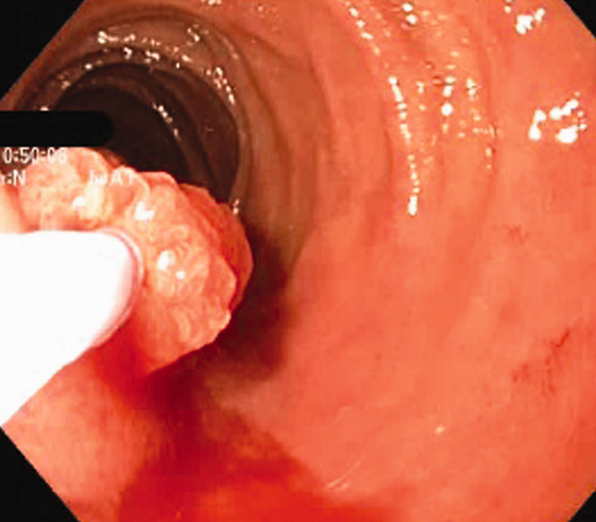

Inflammatory fibroid polyp of the duodenum – Complete endoscopic removal of the IFP (Courtesy Dr. V. Penopoulos)